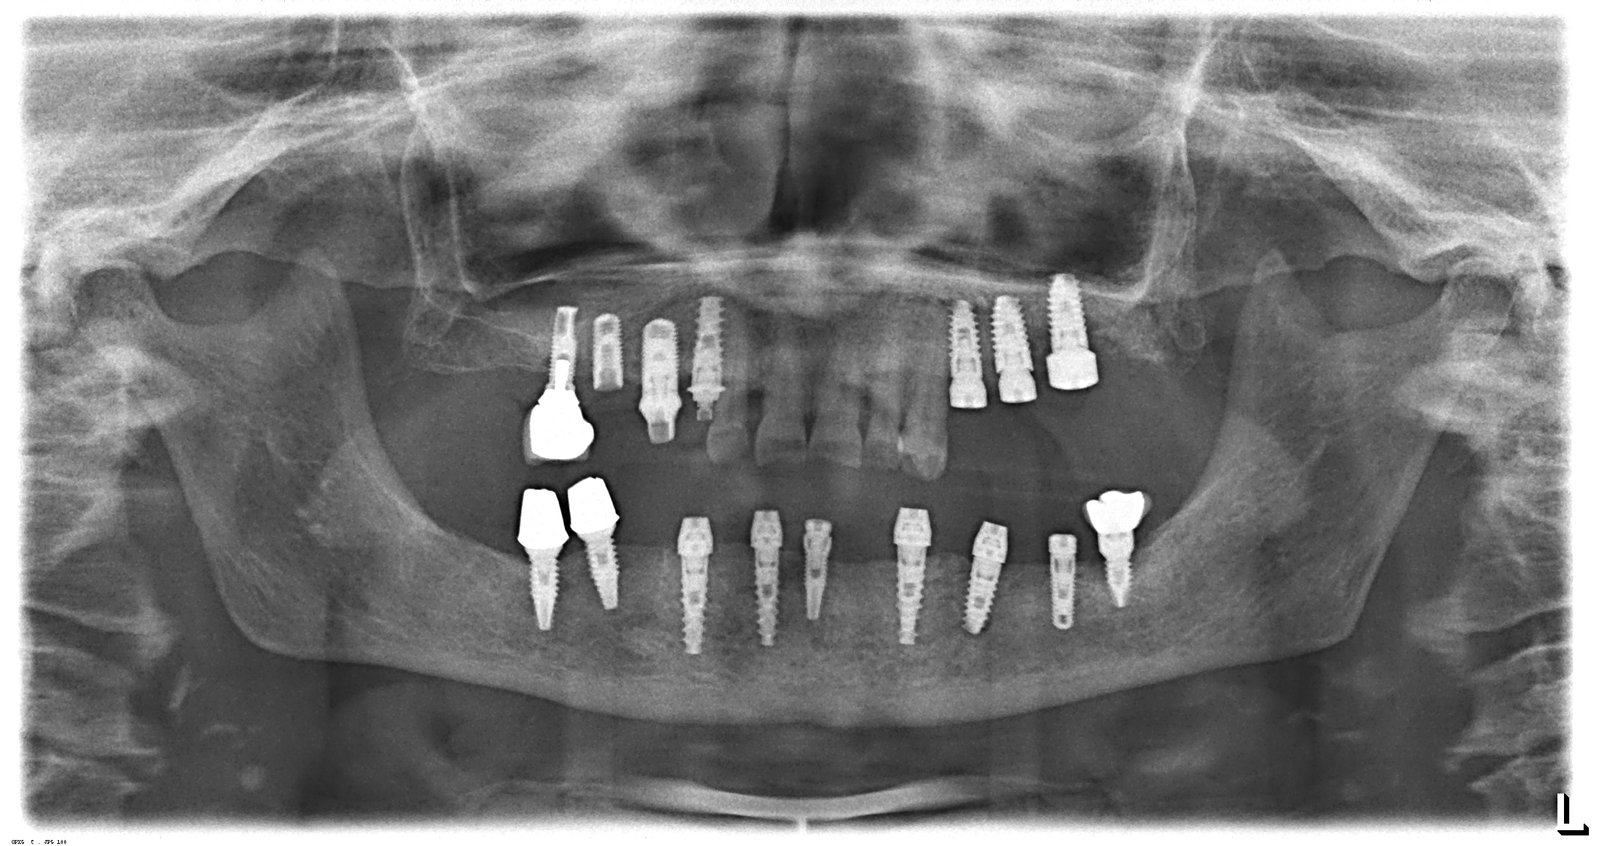

Necesitamos identificar el implante en 34 porque es necesario cambiar la corona. La paciente lleva otros 14 implantes repartidos entre arcada superior e inferior, que le colocaron hace unos 15 [...]